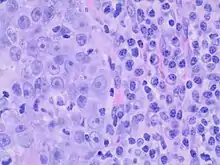

Medullary breast carcinoma is a rare type of breast cancer[1] that is characterized as a relatively circumscribed tumor [2] with pushing, rather than infiltrating, margins. It is histologically characterized as poorly differentiated cells with abundant cytoplasm and pleomorphic high grade vesicular nuclei.[3] It involves lymphocytic (a type of white blood cell) infiltration[4] in and around the tumor and can appear to be brown in appearance with necrosis and hemorrhage.[5] Prognosis is measured through staging but can often be treated successfully and has a better prognosis than other infiltrating breast carcinomas.